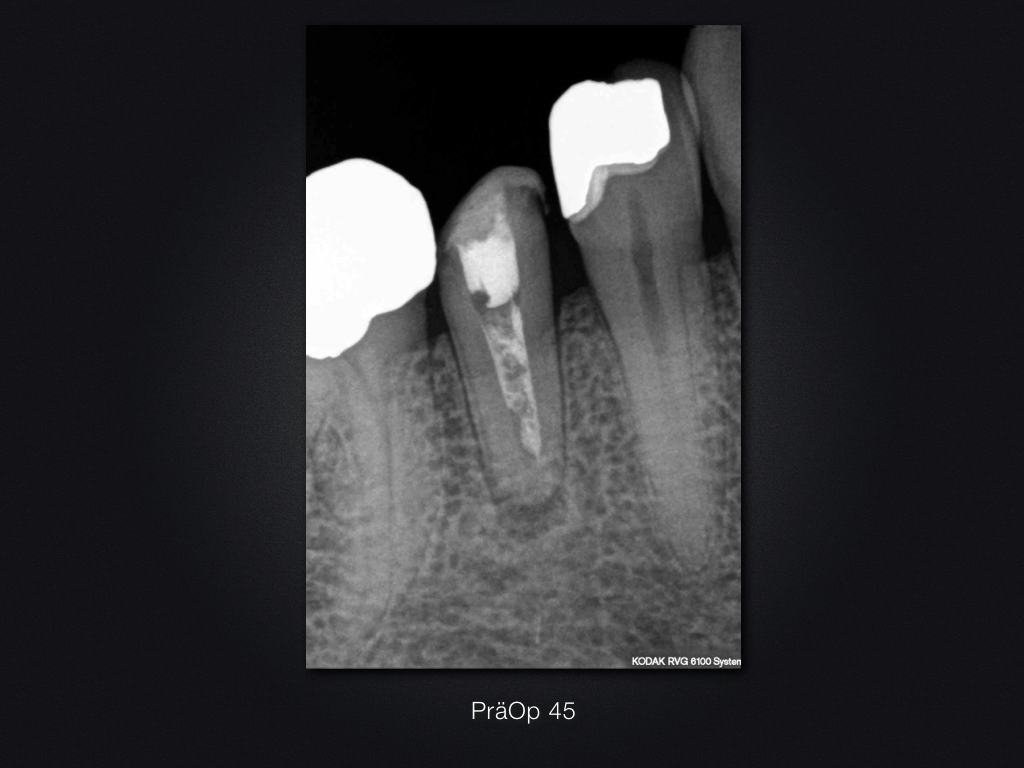

45D.001

1024 × 768

Ofenrohr- das Recall (2)